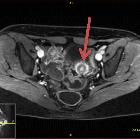

Catamenial

rectal bleeding due to invasive endometriosis: a case report. Transverse T2-weighted magnetic resonance imaging section of pelvis with recto-sigmoid colon endometriosis (red arrow)